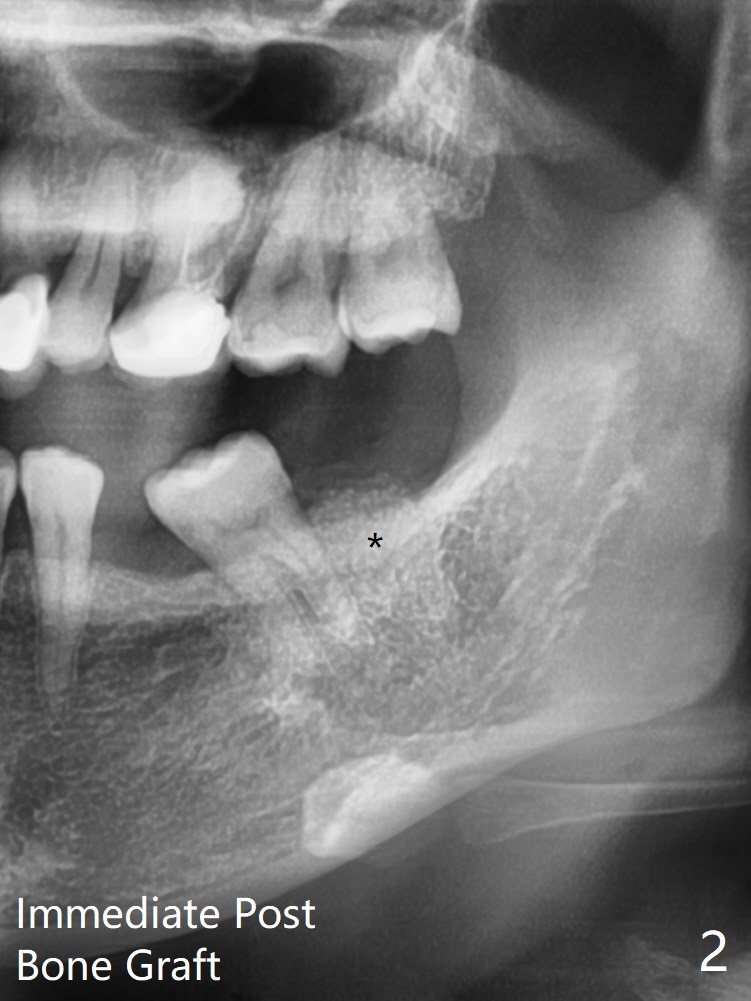

39岁女渴望有一个正常19号牙(图一),第一步,17号牙拔除,粘性骨粉植骨(图二:*),PRF覆盖,树脂敷料。后者术后八天由于倒凹(图三:^),稳定,下面(*)骨粉谅必安居乐业。术后一两个月(伤口愈合,18号牙牙冠远中面充分暴露)后,准备口扫做局部矫正(Clear Aligner),竖直18号牙,植骨有利于18号牙进入17号牙牙槽窝。然后再口扫制作19号牙种植导板。